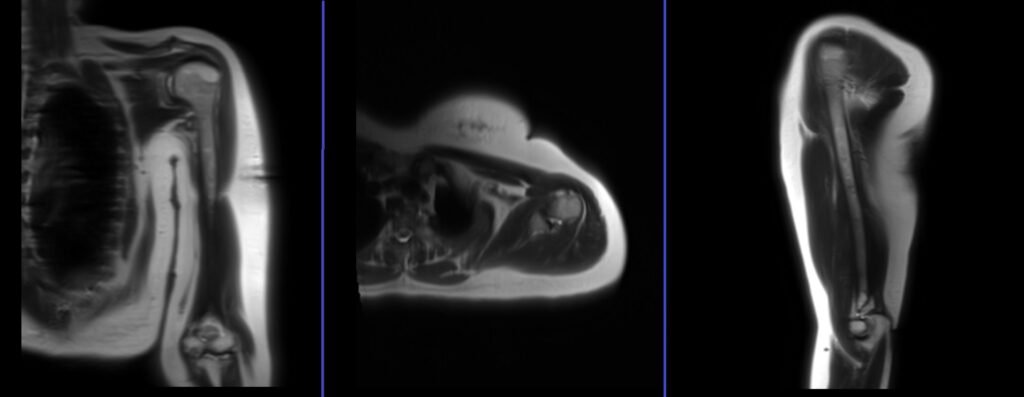

A three-plane localizer must be taken at the beginning to localize and plan the sequences. Localizers are usually less than 25 seconds. T1\T2-weighted low-resolution scans can be used for this purpose. Continue taking additional localizers until a true coronal, axial, and sagittal view of the upper arm is obtained.